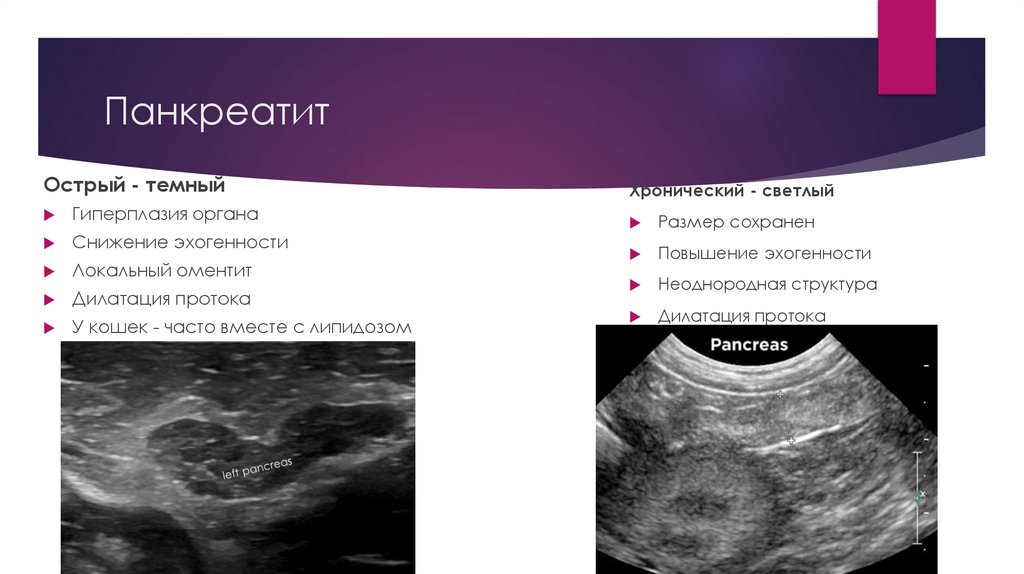

5. Панкреатит

Острый - темный

Гиперплазия органа

Снижение эхогенности

Локальный оментит

Дилатация протока

У кошек - часто вместе с липидозом

Хронический - светлый

Размер сохранен

Повышение эхогенности

Неоднородная структура